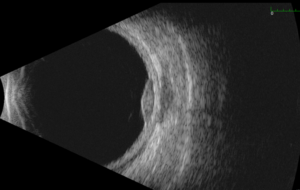

Integrated RECIST + ILD Workflow Enhances Safety Monitoring in an ADC Oncology Program

Summary Interstitial lung disease (ILD) emerged as a potential safety signal within a multi‑cohort antibody–drug conjugate (ADC) oncology program. Recognizing this need early in development, the sponsor study team sought…